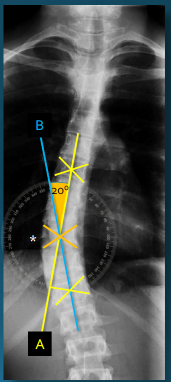

Q what is the name of this measurement? and what is the average + range?

A: Risser-Ferguson Method

assesses the degree of a spinal curvature (scoliosis). No average or range is specified as it is used to measure a pathology.

A: Thoracic Kyphosis

assesses the natural curvature of the thoracic spine. The normal values vary with age and sex.

The mean for individuals aged 20-29 is 26° for males and 27° for females.